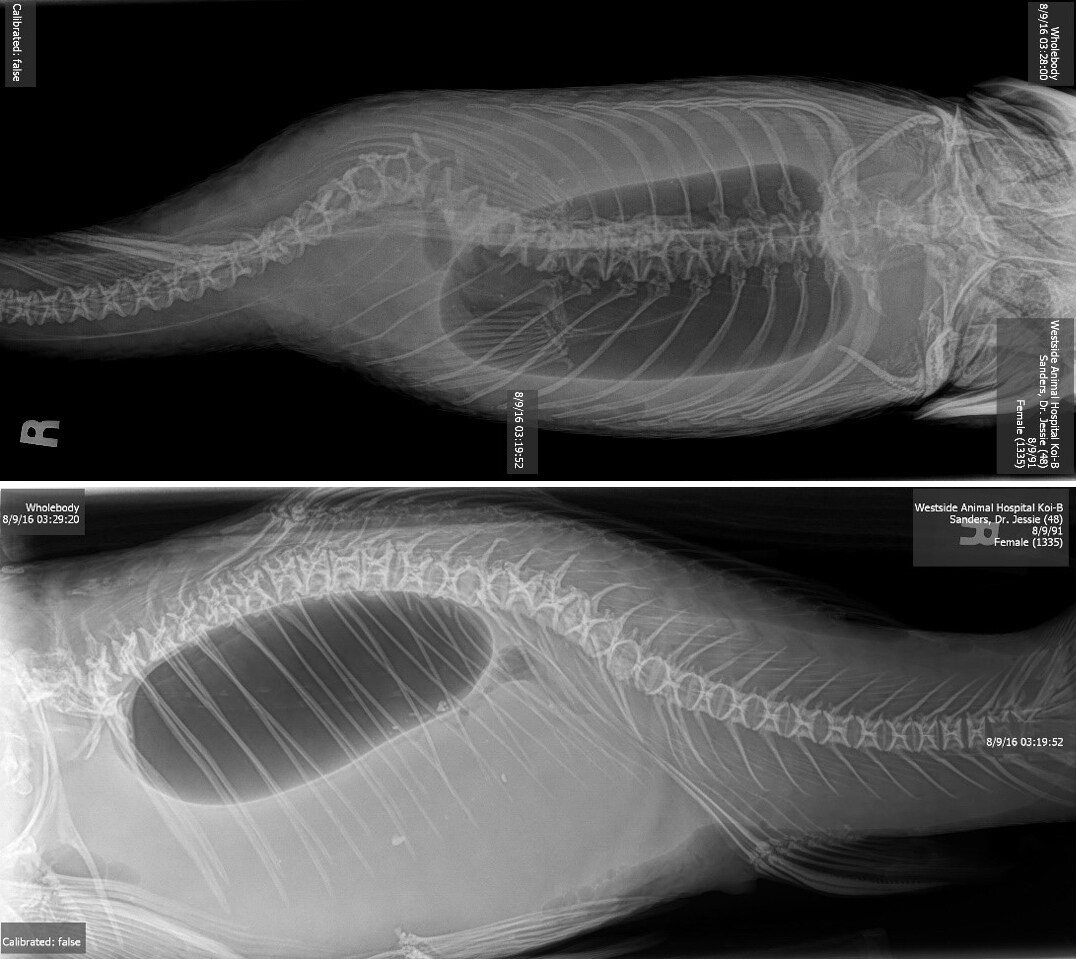

Swim bladder disorders are typically diagnosed using imaging and a review of the fish’s environment and symptoms.

The most effective way to evaluate the swim bladder is through X-rays. Imaging allows veterinarians to clearly assess:

- The size and shape of the swim bladder

- Its position within the body

- The presence of abnormal fluid or displacement

These findings help determine whether the issue is caused by structural changes, infection, or another underlying condition.

Koi

Koi are also susceptible to swim bladder issues, particularly when affected by spinal deformities or neurological conditions.

Over time, the swim bladder may change in size or shape to compensate for reduced mobility. These adaptations can help the fish survive but are often permanent.